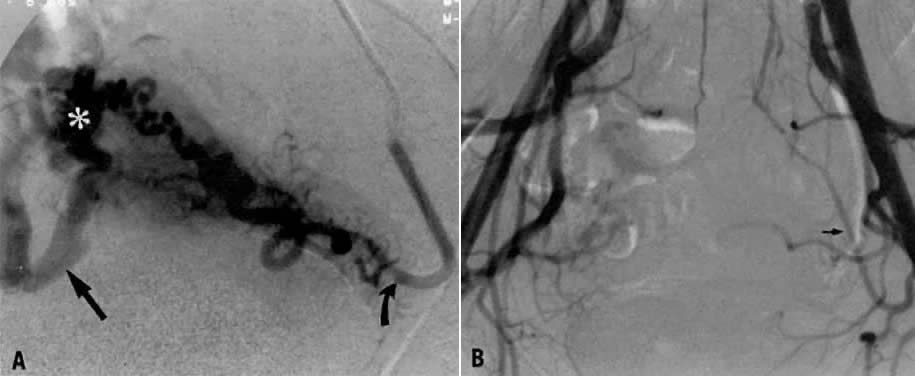

This 35-year-old woman (gravida 2, para 2) had brisk and unremitting hemorrhage after forceps delivery of a healthy term infant. A cervical laceration was found and sutured; however, the patient continued to bleed; 5 units of whole blood were administered. Despite uterine and vaginal packing, bleeding continued. In an effort to avoid hysterectomy, arteriography and embolization were requested. Selective left uterine arteriography (Fig. 18A), performed from the right common femoral approach, showed the typical appearance of the uterine artery and its branches postpartum. Although no extravasation was seen, the brisk hemorrhage (presumably from a descending cervical branch of the uterine artery) prompted the use of embolization with surgical gelatin pledgets. This intervention resulted in complete occlusion of the uterine artery (Fig. 18B). The right uterine artery also was embolized, resulting in prompt cessation of bleeding.

Fig. 18. Case 1. Forceps-related cervical laceration. A. Left uterine arteriogram with postpartum changes and no extravasation of contrast. B. Complete occlusion of left uterine artery ( arrow) after embolization with surgical gelatin pledgets.

Case 2.

This 26-year-old woman (gravida 2, para 1) underwent dilatation and curettage for a missed abortion and bled briskly after the procedure; the bleeding did not respond to conventional measures. To preserve reproductive function, embolization was carried out bilaterally. Figure 19 represents the left (Fig. 19A) and right (Fig. 19B) uterine artery injections, both of which were performed from a right common femoral approach. Of note is the typical spiral endometrial artery pattern of the right uterine artery. Here also, no specific bleeding was demonstrated, but bilateral selective uterine embolization with surgical gelatin produced complete occlusion of the left (Fig. 19C) and right (Fig. 19D) uterine arteries with prompt cessation of the hemorrhage.

Fig. 19. Case 2. Bleeding after dilatation and curettage. A. Left uterine artery injection. B. Right uterine artery injection. Note typical spiral endometrial pattern without contrast extravasation. C and D. Images after bilateral embolization with surgical gelatin ( arrow ).